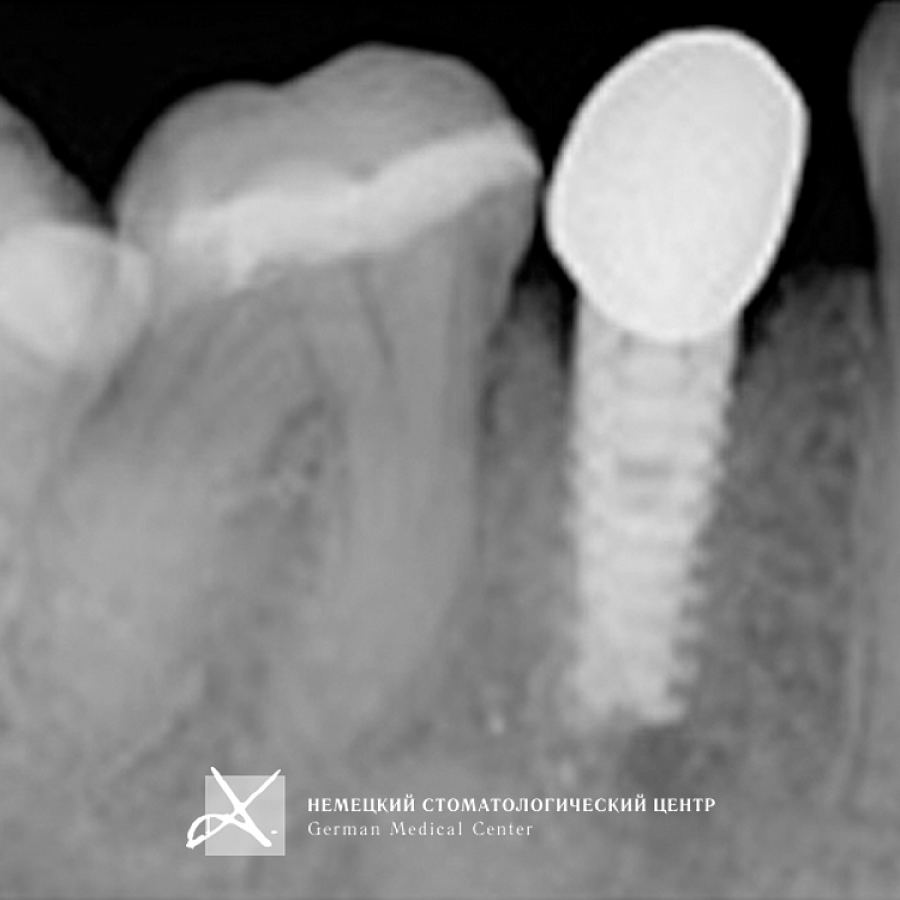

Учитывая тот факт, что диаметр имплантата практически всегда вынужденно меньше диаметра восстанавливаемого зуба в данной анатомической области, чтобы получить максимально эстетический и функциональный результат, было сделано:

- Поэтапное "выстраивание" десневого контура ("кратера прорезывания") с помощью индивидуально моделируемой диагностической промежуточной коронки и индивидуально построенной супраструктуры (абатмента), выполненной из золотосодержащего сплава.